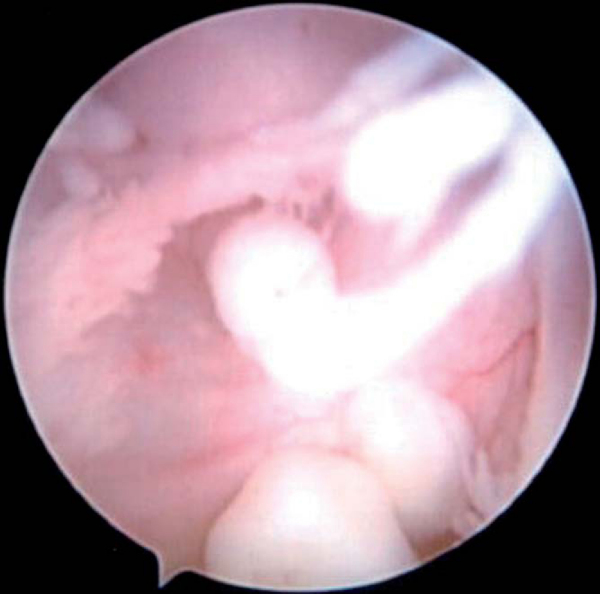

Traumatic chondral defects and osteochondritis of the humeral head or glenoid result in irritation and swelling within the glenohumeral joint. Finding these loose articular pieces within the shoulder joint and their removal will help decrease symptoms (

Fig. 7-7

). The injured bed in the articular surface should also be located and débrided and at least marrow stimulation performed.